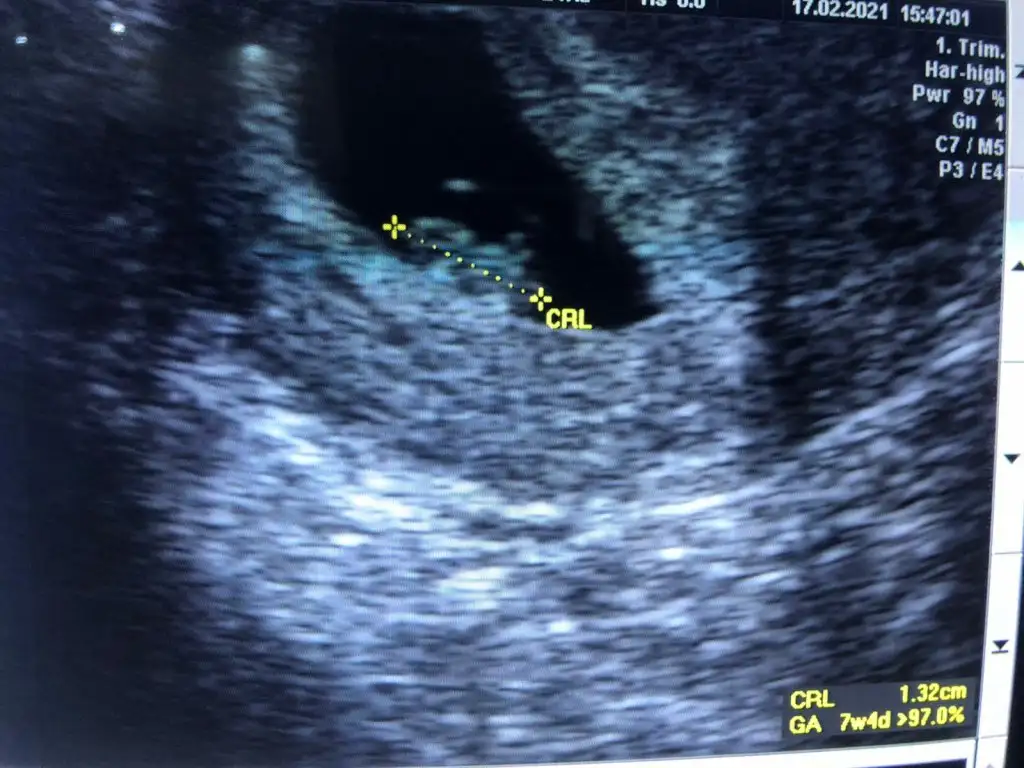

Bana da tahmin yaparmısınız rica etsem :)

Eklentiler

• WhatsApp Image 2021-02-13 at 12.55.22 (1).webp

WhatsApp Image 2021-02-13 at 12.55.22 (1).webp

25,2 KB · Görüntüleme: 91